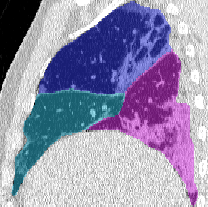

Lobar Segmentation

Lobar segmentation results for the proposed method and PTK are shown in Figure 5 for right lungs and Figure 6 for left lungs. For each image in the COVID-19 dataset (133 images in total), the lobar segmentation result was used to extract the amount of poor aeration () and consolidation () in each lobe. Common phenotypes of COVID-19 affected lungs were identified by hierarchical clustering over the fraction of poorly aerated and consolidated tissue in each lobe. Dendrographic analysis in Figure 7 reveals four primary clusters of patients that were identified by the hierarchical clustering: (a) mild loss of aeration primarily in the two lower lobes without consolidation; (b) moderate loss of aeration focused in the two lower lobes with or without consolidation in lower lobes; (c) severe loss of aeration throughout all lobes with or without consolidation; and (d) severe loss of aeration and consolidation throughout all lobes.

| CT Image | PTK | Proposed |